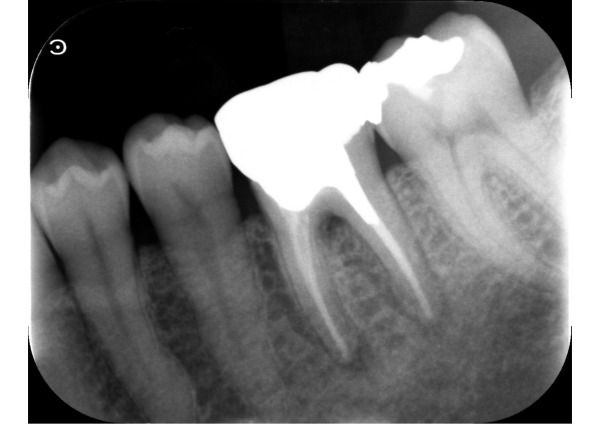

患者様は、左下の歯ぐきの腫れを主訴に、セカンドオピニオン希望で来院されました。7年ほど前に根管治療した歯がうずくとのことで、お口を拝見すると腫れた歯ぐきに膿を排出するための穴(サイナストラクト)ができていました。エックス線写真を撮ると、歯根を囲むように大きな黒い透過像が認められました。

1日目〜2日目 被せ物と土台を外し、根管治療を始めました。歯周ポケット検査では、左下6番は一部8mmと深くなっており、歯根が破折している可能性を患者様へご説明しました。

3日目 CT撮影の結果、骨が広範囲に溶けていることが判明したため、その状況をご説明し、抜歯をご提案しました。